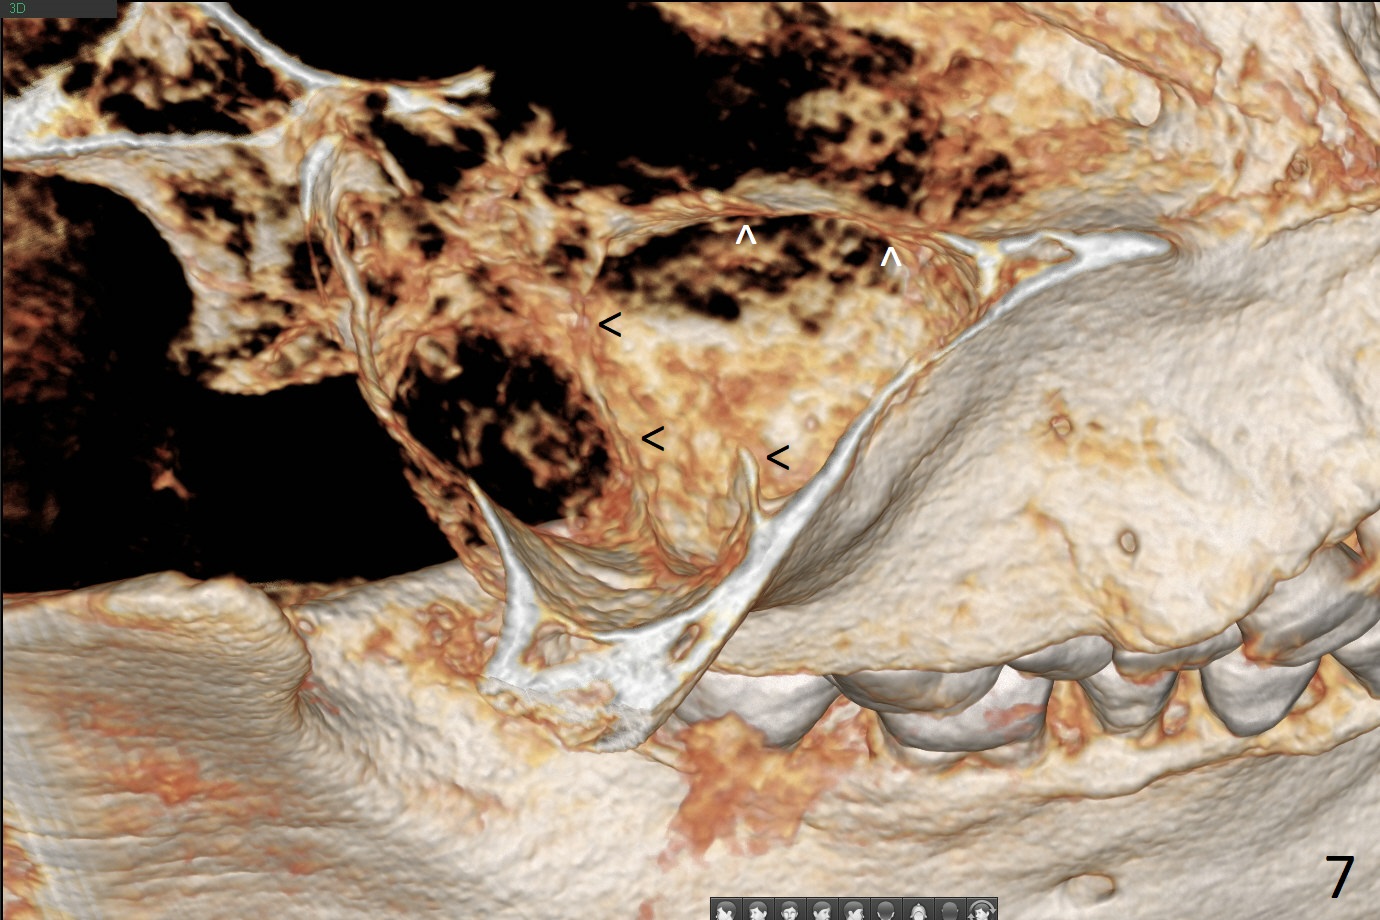

A 51-year-old man agrees to have #2 residual root to be extracted for implant. Panoramic X-ray (Fig.1) and CT coronal section (Fig.2) show maxillary sinus mucocele (*). A 5x10 mm implant will be placed not to intrude into the sinus (Fig.2,3). In case sinus membrane perforation, prepare PRF membranes for repair. The apex of the implant will be engaged to an apparent sinus septum for stability (Fig.4,5,7 arrowheads). Fig.4,5,6 are sagittal and coronal sections and 3-D image of Fig.3 without an implant at #2, while Fig.7 is the inferior view of Fig.6 (arrow).